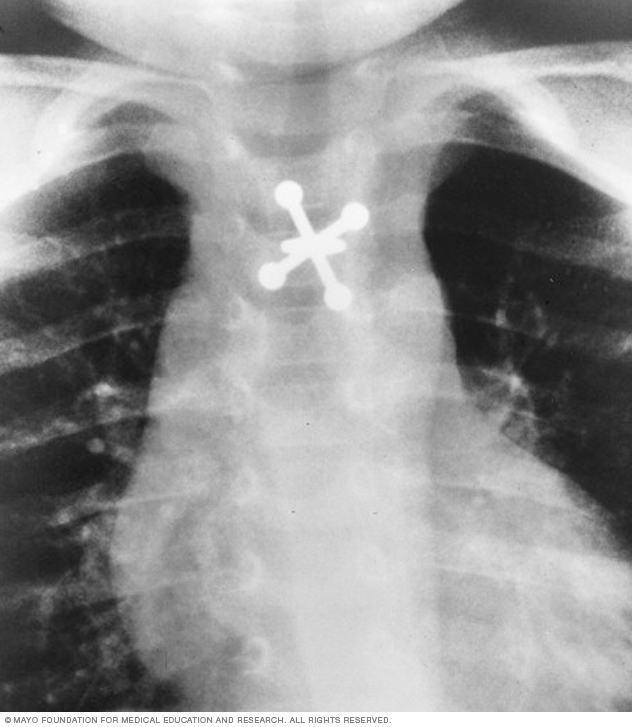

X-ray of swallowed jack

X-rays can locate metal objects your child has swallowed, such as this jack.